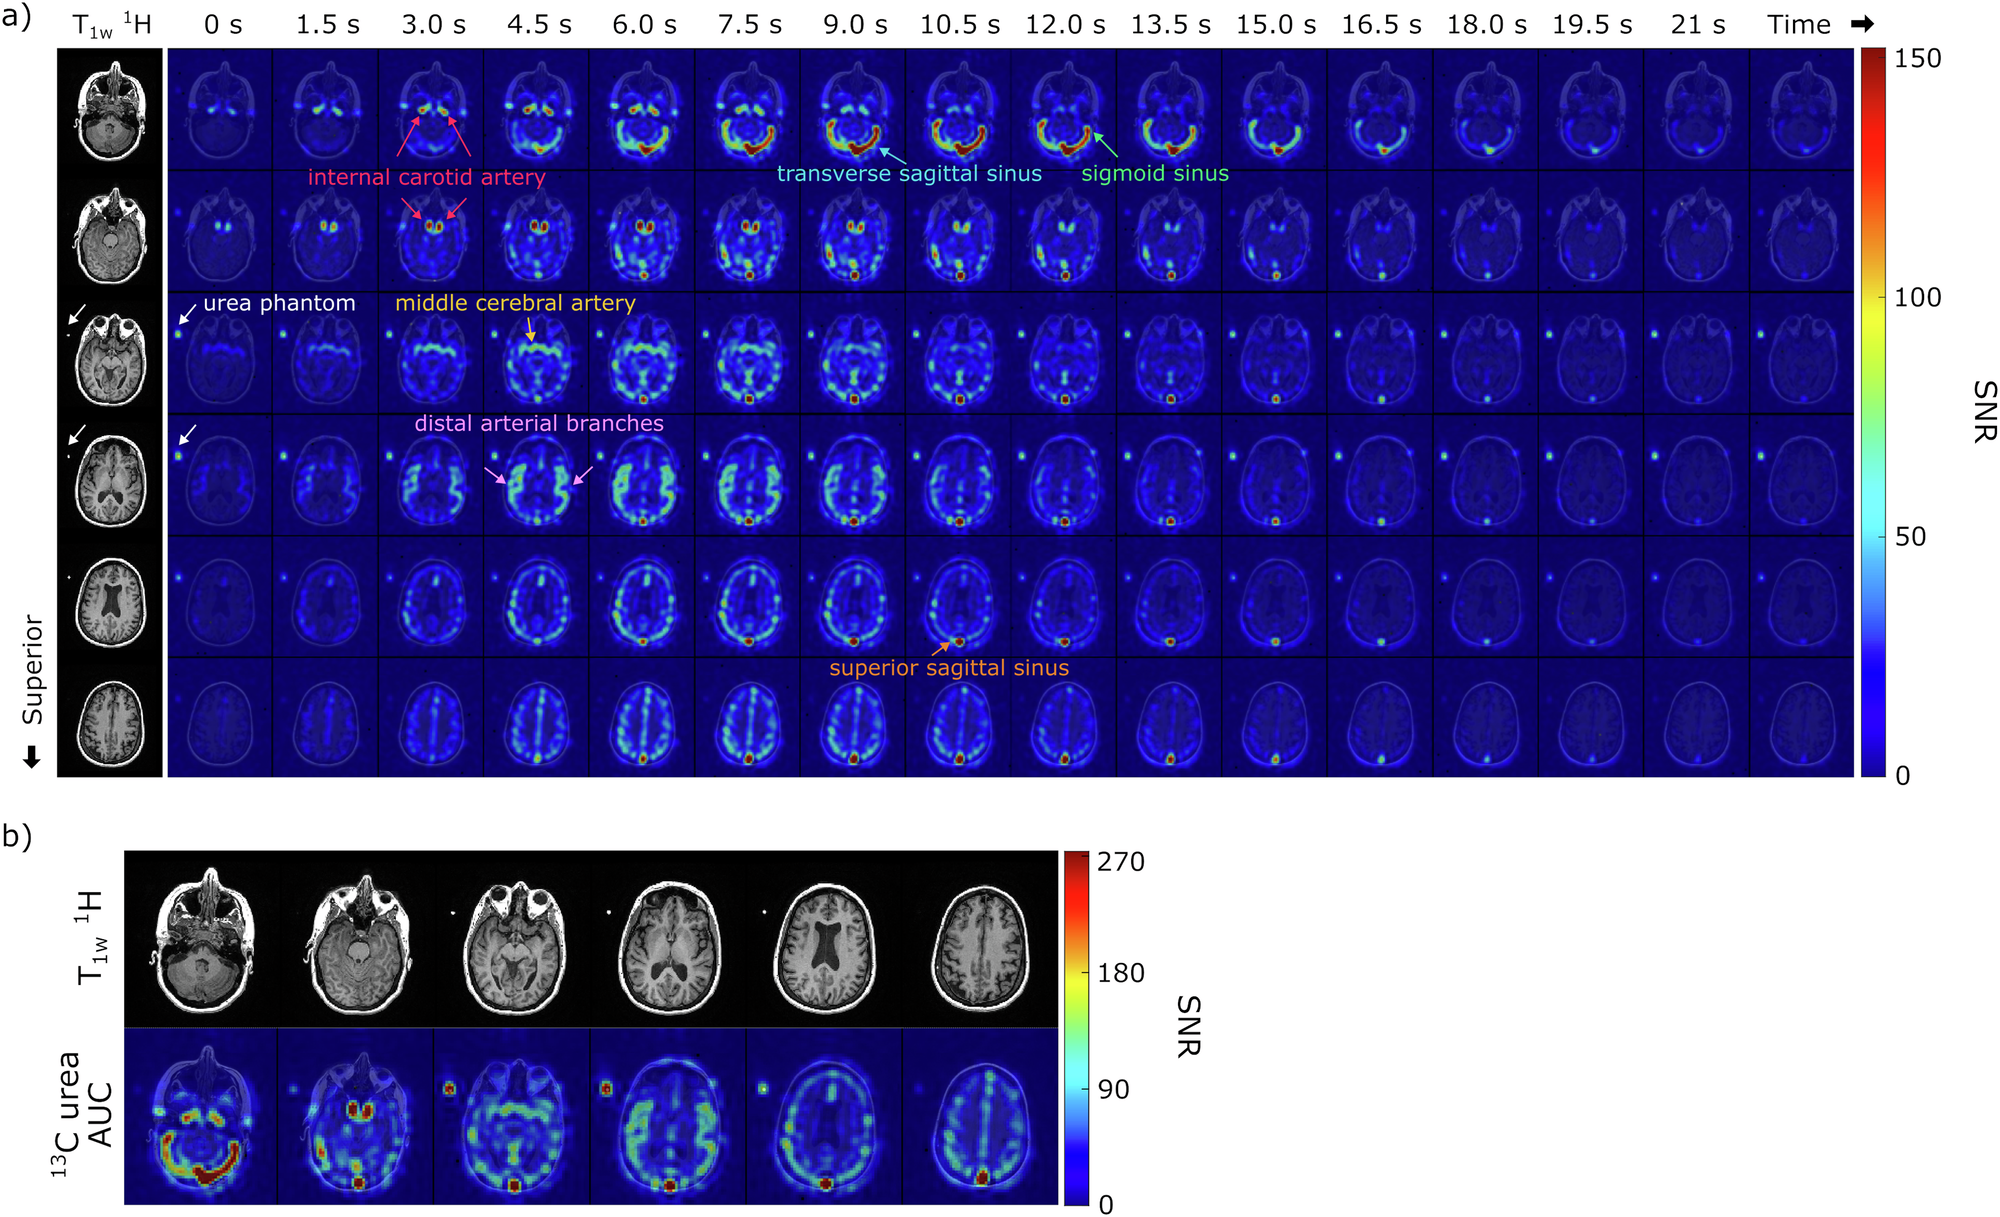

Fig. 2: Representative hyperpolarized [13C,15N2]urea images from a healthy brain volunteer.

a Corresponding 1H anatomical images and the dynamic HP [13C,15N2]urea images (7.76 × 7.76 × 15 mm3) overlaid on the 1H anatomical images are displayed. A total of 20 slices and 32 timeframes were acquired, and this figure displays the middle 6 slices and the first 16 timeframes (1.5 s temporal resolution). White arrows indicate the signal from the urea phantom. b Total signal (area-under-curve, AUC) images of urea from the same subject. The urea images overlaid on the corresponding 1H anatomical images are shown.